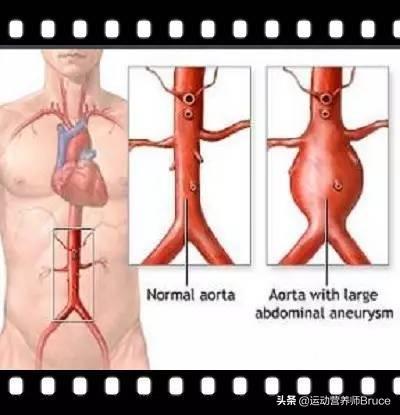

La plaque la plus grave est la plaque cardiovasculaire, ou plaque carotidienne, dont l'aggravation entraîne une ischémie myocardique, une ischémie cérébrale ; si elle n'est pas activement contrôlée, la plaque peut même se rompre et se thromboser, entraînant un infarctus du myocarde ou un infarctus cérébral.

L'athérosclérose est fréquente à 80 % chez les personnes de plus de 50 ans, et l'incidence des plaques carotidiennes augmente avec l'âge. Chez quelques personnes âgées, les plaques conduisent à une sténose, qui peut entraîner des changements hémodynamiques et même une obstruction.

L'incidence des plaques a augmenté de manière significative chez les patients âgés de plus de 60 ans par rapport aux patients âgés de 50 à 59 ans, alors que la différence d'incidence des plaques chez les patients âgés de plus de 60 ans était faible, ce qui indique que l'incidence des plaques a augmenté de manière significative chez les personnes âgées par rapport aux personnes d'âge moyen.

L'athérosclérose est une lésion endothéliale des vaisseaux sanguins artériels dont souffre tout adulte, même à partir de l'adolescence. Elle se développe lentement au fil des décennies et finit par former des plaques d'athérome qui obstruent les vaisseaux sanguins ou provoquent leur rupture, entraînant de graves maladies cardiovasculaires et cérébrovasculaires, telles que l'hémorragie cérébrale, l'infarctus cérébral, la maladie coronarienne et la séparation de la coarctation aortique.

Il existe une méthode appelée endartériectomie carotidienne qui permet de retirer la paroi de l'artère carotide gravement malade et de réduire le risque d'infarctus cérébral. L'opération présente toutefois certains risques ; l'artère carotide est sujette à la thrombose après l'opération lorsque l'artère carotide intacte est manquante, et le traitement anti-thrombotique lui-même a de nombreux effets secondaires. Il existe également des techniques médicales telles que la pose d'un stent, la dilatation par ballonnet et la thrombolyse par ballonnet, qui permettent d'ouvrir les vaisseaux sanguins rétrécis. Toutes ces méthodes sont localisées, elles traitent les symptômes mais pas la cause profonde et n'éliminent pas la plaque au sens propre du terme.